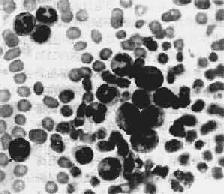

1.血象 Hb輕中度減低,Plt減少,半數在50×109/L以下,白細胞增多,2/3患兒在50×109/L以下,少數患兒(<10%)大於100×109/L單核細胞增多外周血出現幼粒細胞和幼紅細胞嗜酸細胞和嗜鹼細胞可增多但不似Ph1CML明顯